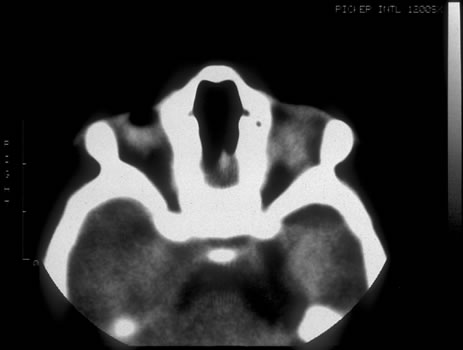

Fig. 3. Infant with severe microphthalmos secondary to fetal alcohol syndrome.

Fig. 4. Computed tomography scan of infant with severe microphthalmos secondary to fetal alcohol syndrome.

Fig. 5. Segmental corneal opacification consistent with Peter's anomaly seen in fetal alcohol syndrome.